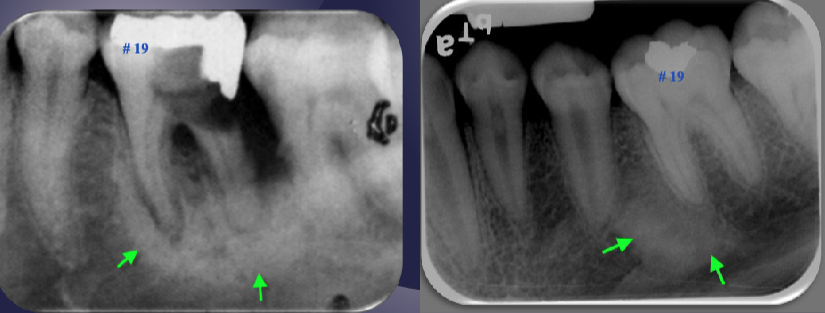

differentiate the pathology of the 2 images

left: loss of apical lamina dura + periapical radiolucency

right: normal lamina dura + radiolucency due to submandibular fossa

left: widened PDL + periapical radiopaque area + non-vital tooth → sclerosing osteitis

right: normal PDL + periapical radiopaque area due to dense bone island + vital tooth → normal